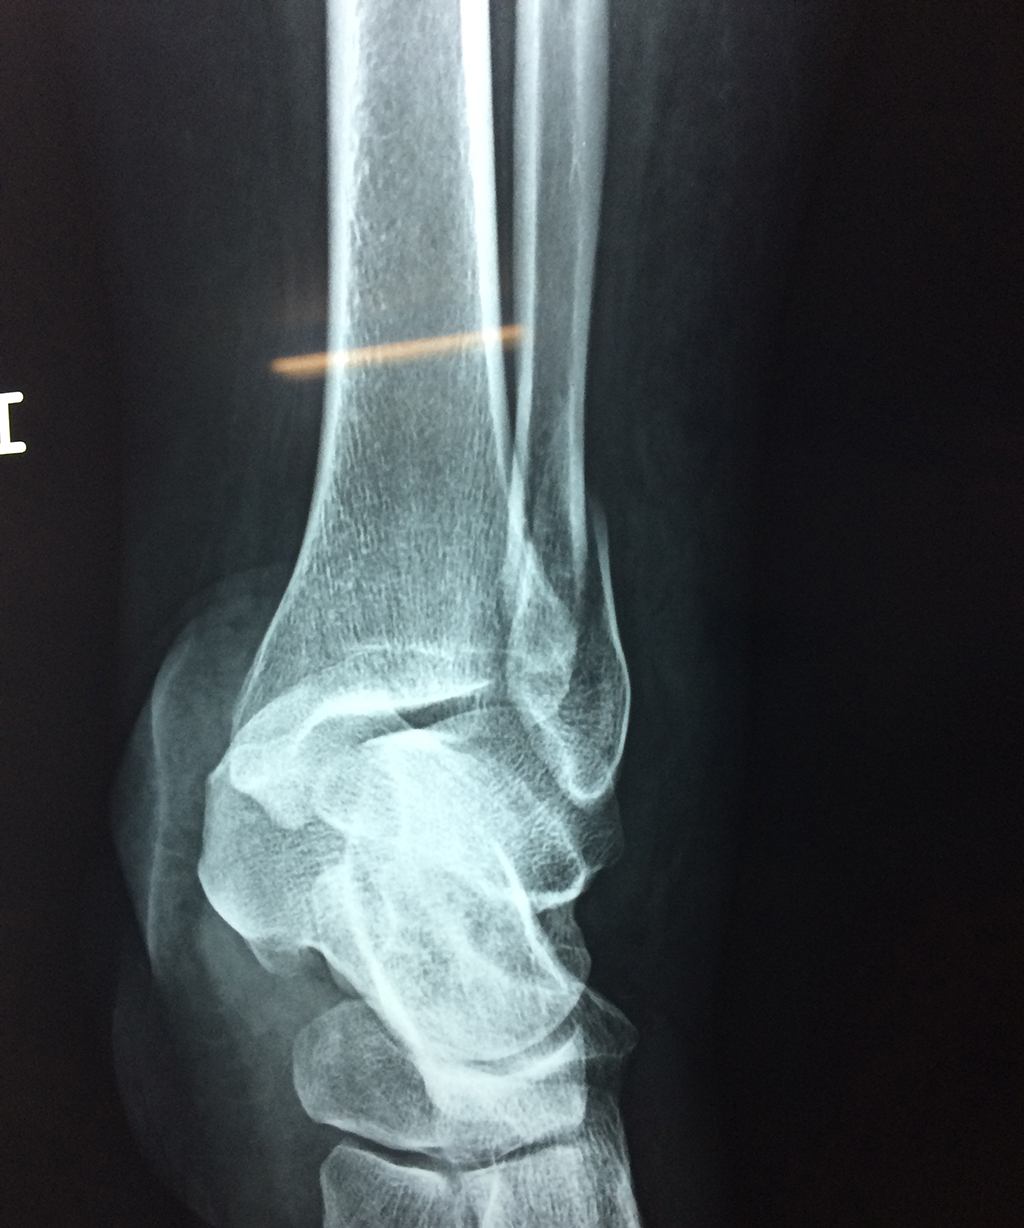

Una fractura de tobillo es la rotura de uno o más de los huesos del tobillo. Estas fracturas pueden ser:

Algunas fracturas de tobillo pueden requerir cirugía si:

• Los extremos de los huesos están desalineados entre sí (desplazados).

• La fractura se extiende hasta la articulación del tobillo (fractura intra-articular).